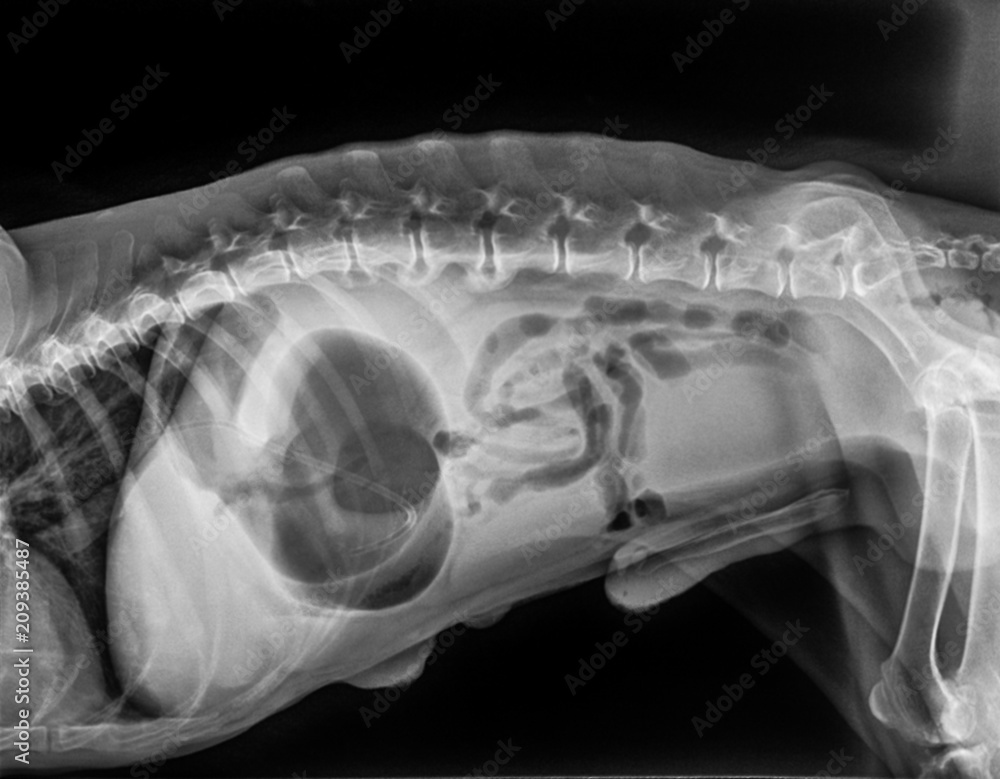

From stock.adobe.com

Xray of dog lateral view with Gastric dilatation volvulus “GDV” or What's It Called When A Dog's Stomach Twists stomach flip, also known as bloat, or in medical terms, gastric dilatation volvulus (gdv), is the expansion of the dog's stomach due to the. a dog stomach flip is a serious condition that affects a dog’s digestive system and is known by many different names, such as gastric. gdv occurs when the dog’s stomach fills with air. What's It Called When A Dog's Stomach Twists.